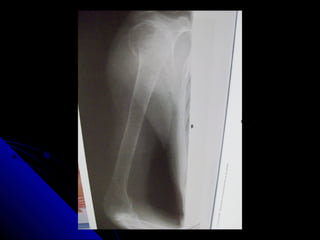

PROYECCION LATERALPROYECCION LATERAL

 Se flexiona el codo y se centra elSe flexiona el codo y se centra el

antebrazo.antebrazo.

 En una posiciòn lateral verdadera, elEn una posiciòn lateral verdadera, el

radio y el cùbito en su extremo distal,radio y el cùbito en su extremo distal,

quedan superpuestos-quedan superpuestos-

 La cabeza radial queda superpuesta a laLa cabeza radial queda superpuesta a la

apòfisis coronoides.apòfisis coronoides.

 La tuberosidad radial se ve de frente.La tuberosidad radial se ve de frente.

 Epicòndilo y epitròclea , superpuestos.Epicòndilo y epitròclea , superpuestos.